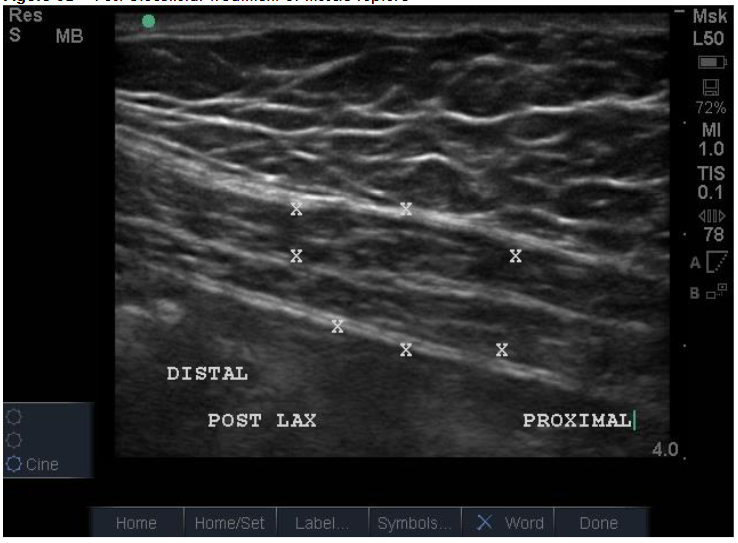

Figure 7A: Pre-Treatment Medial Meniscal/MCL Damage and Inflammatory Changes. Figure 7B: Post-Treatment with Biocellular Product (Orthobiologic) mix of Nanofat + HD PRP, this target Medial Meniscus areas (1 target of many in Knee).

Muscular/Scar Repair: The ability of the biocellular mixture in the repair of torn, damaged or failed muscular structures is quite remarkable. This is accentuated in light of the difficulties relative to internal muscle repair of damage as seen in trauma or invasive surgery. Often rapid responses are realized, with both avoidance of scarring OR the reduction of scarring present has been well shown in many clinical cases. With enhanced vascularity and perfusion within the damaged muscular tissues, limited or less scar formations are important advantages. Some Providers define a ”toxic” inflammatory reactions as those that lead to tissue scarring. This is seen in unstable or excessive inflammatory scar reactions which are not desirable. Avoidance of excesses or hypertrophic scarring is a clear advantage to wound healing and long-term outcomes for patients. Nanofat stem/stromal elements are capable of forming smooth, skeletal and cardiac muscle. Biocellular therapy helps a more stable and less inflammatory environment. This coupled with the existing damaged muscle can lead to excellent reformation and return to function. This modality is becoming very common to include direct intramuscular guided placements to improve the internal architecture (sonographic echotexture restoration), and confirmed with dynamic testing of the musculature during the ultrasound from diagnostic and treatment when tracked in follow up examinations.